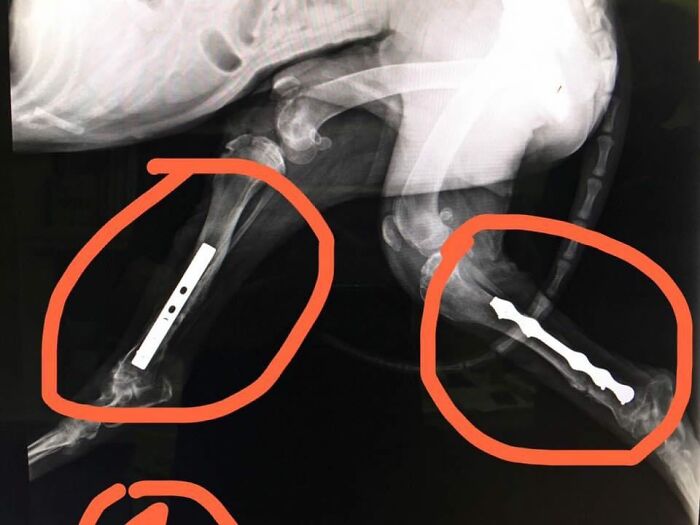

Owen’s legs were broken and he could not walk, so he needed special treatment

A hospital said his feet couldn’t be saved and he would have to be sacrificed, but Goody Wu didn’t give up on him

Fortunately, the woman found a good doctor at another hospital who performed surgery and helped the dog to recover